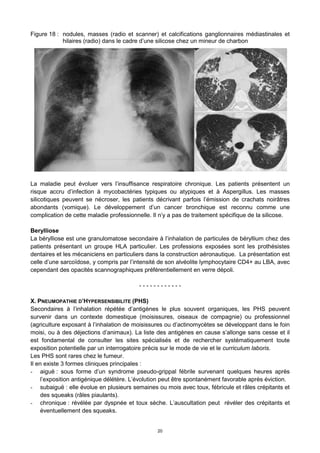

Figure 18 : nodules, masses (radio et scanner) et calcifications ganglionnaires médiastinales et

hilaires (radio) dans le cadre d’une silicose chez un mineur de charbon

L’imagerie thoracique montre des opacités micronodulaires diffuses prédominant dans les lobes

supérieurs, pouvant confluer jusqu’à donner des masses pseudo-tumorales caractéristiques

(Figure 18). Des adénopathies médiastinales contenant des calcifications « en coquille d’œuf »

La maladie peut évoluer vers l’insuffisance respiratoire chronique. Les patients présentent un

risque accru d’infection à mycobactéries typiques ou atypiques et à Aspergillus. Les masses

silicotiques peuvent se nécroser, les patients décrivant parfois l’émission de crachats noirâtres

abondants (vomique). Le développement d’un cancer bronchique est reconnu comme une

complication de cette maladie professionnelle. Il n’y a pas de traitement spécifique de la silicose.